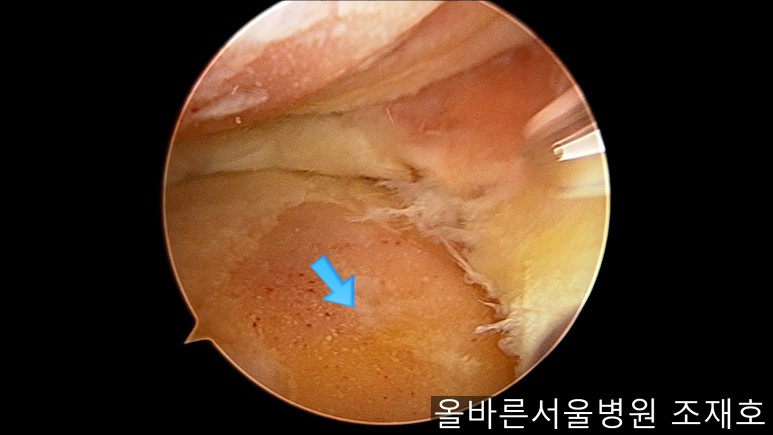

通过关节镜图像可看到:由于内侧股骨髁软骨损伤骨头已经显露出来。

胫骨上端的软骨损伤严重,也露出了骨头。

正是缺失软骨的部位碰到一起,引发剧烈疼痛,腿部逐渐变形。